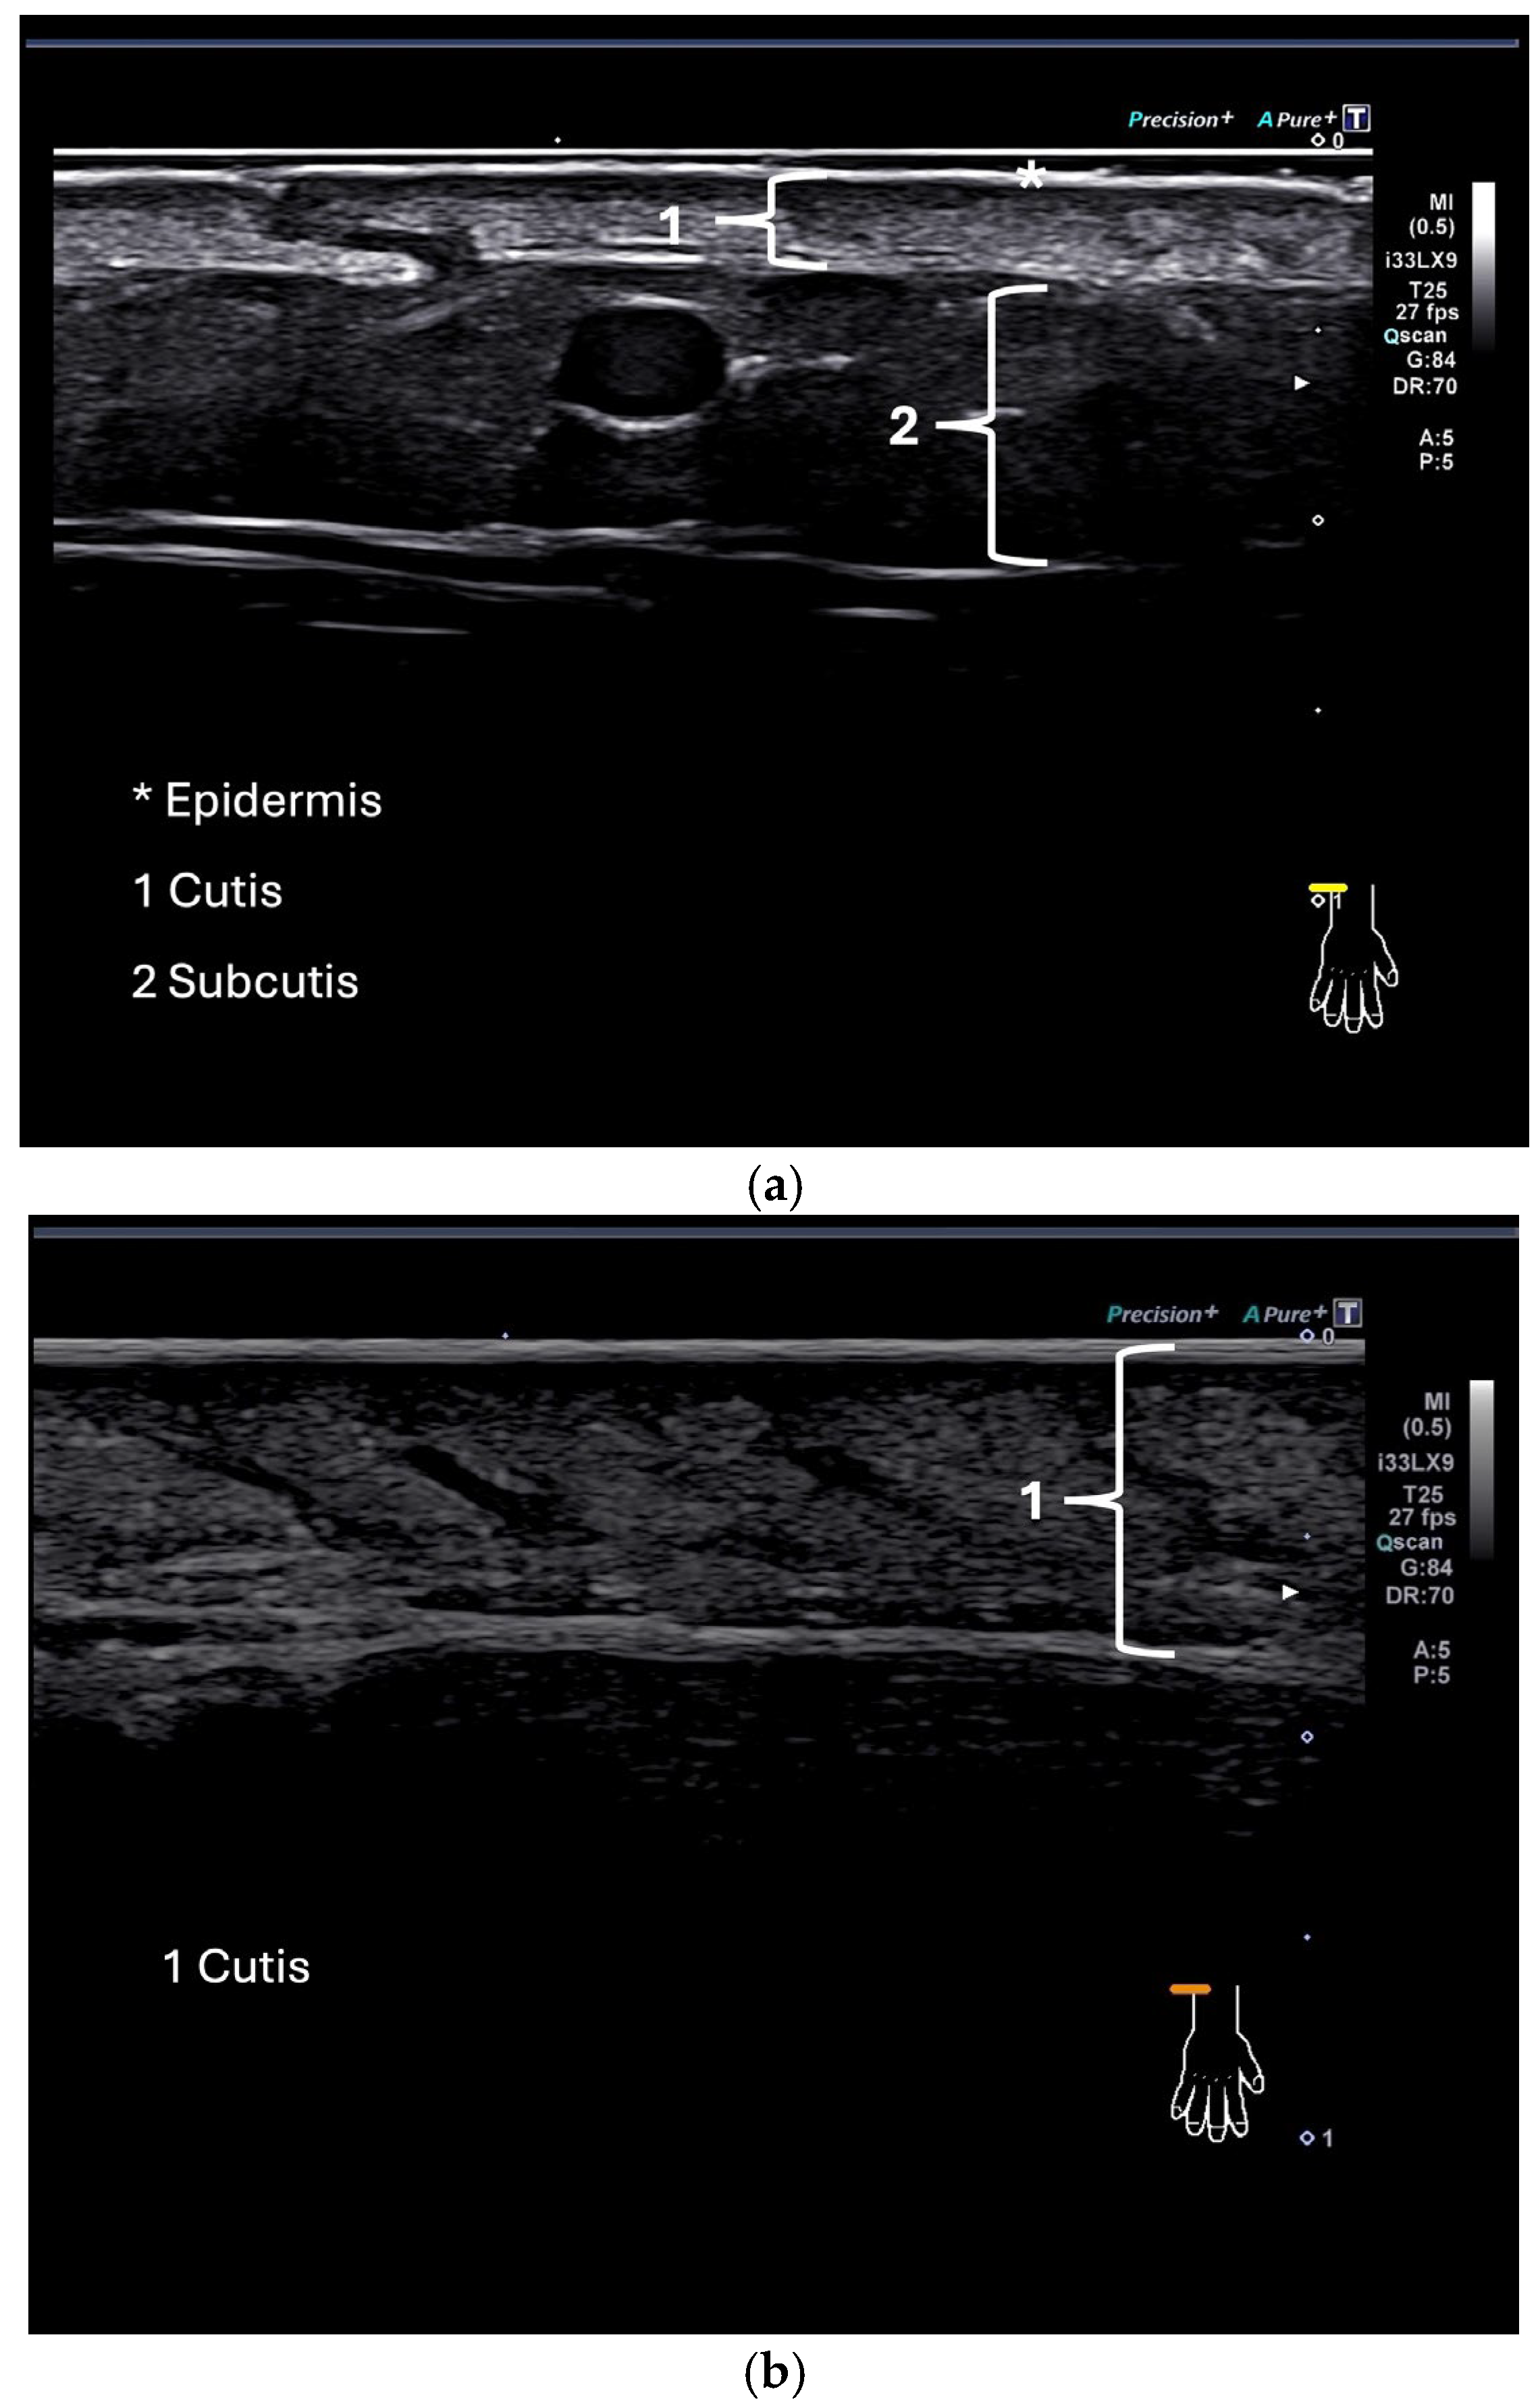

Examples of ultrasound images of the dorsal side of the forearm in a healthy control and a patient with SSc are given in Figure 2.

Figure 2.

(a,b) Ultrasound image showing the skin of a healthy control at the dorsum of the forearm (a); ultrasound image of the skin of a patient (b).